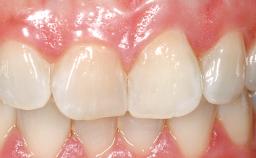

Immediate Placement of an Implant in a Maxillary Right Central Incisor Site

A 30-year-old female patient was referred to the office for the treatment of tooth 11. Her chief concern at the initial visit was to inquire, “Why is my tooth pink?” Upon clinical examination, it was determined that tooth 11 had a previous history of trauma and that the clinical crown had become noticeably pink in color as a result of internal resorption. This diagnosis was confirmed radiographically, indicating a large radiolucency involving the central and distal portions of the clinical crown. It was determined that restoration of this tooth was not possible, and that extraction was indicated. The presence of a mid-line diastema, which the patient wanted to reproduce, directed the treatment plan for tooth replacement utilizing a dental implant.

Patient's Esthetic Expectations Low Medium High

Esthetic Risk High